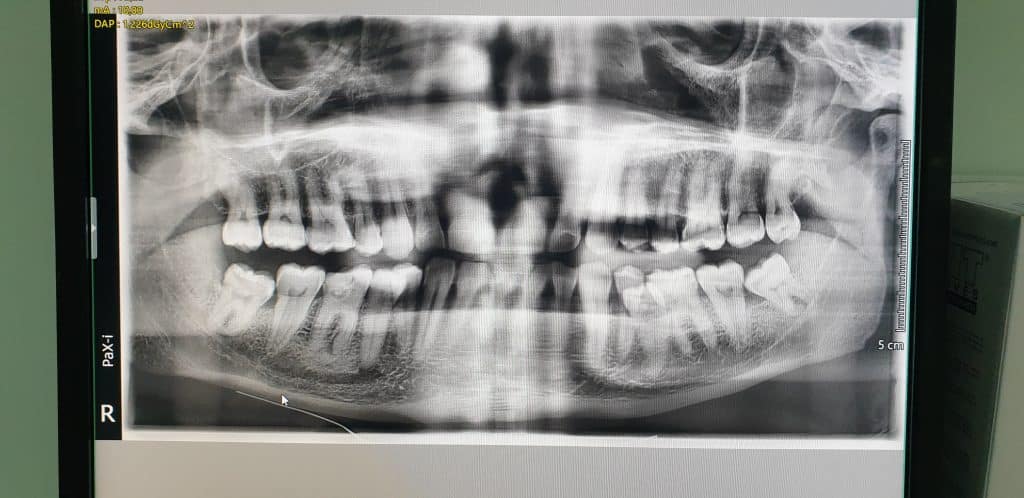

All’esame clinico si evince la posizione anomala del 3.5 e dopo aver effettuato OPT, si opta per l’avulsione dell’elemento dentario interessato.

L’avulsione ha presentato un discreto livello di difficoltà vista la posizione e lo stretto rapporto col 3.4, tanto da ipotizzare l’avulsione anche del 3.4.